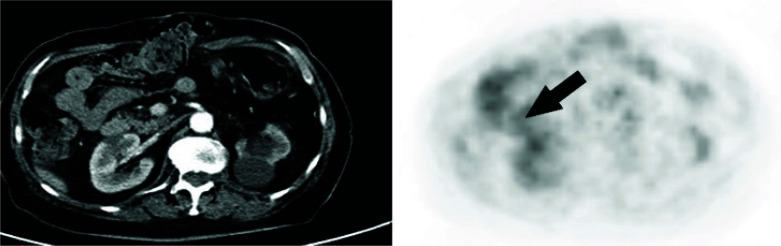

Immunotherapy has revolutionized the treatment landscape for solid tumours. Here, we describe the case of a 69-year-old woman with advanced endometrial cancer (EC) who achieved prolonged disease control with immunotherapy. The patient was diagnosed with stage IIIC EC in February 2020 and was treated with carboplatin and paclitaxel, followed by radiotherapy. Relapses occurred in February 2021 (treated with doxorubicin and palliative radiotherapy) and July 2022 (treated with a carboplatin rechallenge). Pembrolizumab and lenvatinib were started in November 2022. Although the initial scan showed progressive disease, restaging 2 months later showed stable disease, which was maintained on pembrolizumab and lenvatinib until progression in October 2024. This article is part of the New treatment options for advanced endometrial carcinoma Special Issue: https://www.drugsincontext.com/special_issues/new-treatment-options-for-advanced-endometrial-carcinoma.

Abstract Image